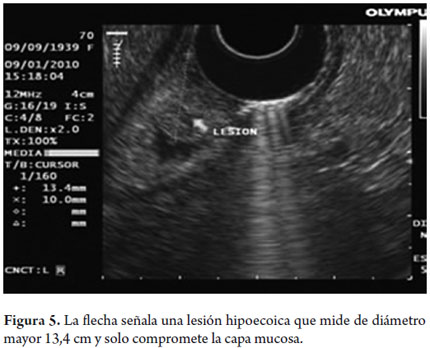

Se trata de una paciente de 75 años con síntomas dispépticos sin signos de alarma. Se realiza EVDA encontrando una lesión levantada de 20 mm en la región prepilórica clasificada como una lesión tipo 0-I (figura 3). Se realiza mucosectomía endoscópica con el método de levantar y cortar con asa lográndose una resección completa, no hay complicaciones (figura 4). Previamente se había realizado una ecoendoscopia la cual muestra compromiso del tumor solo de las dos primeras capas ecográficas, es decir la mucosa (figura 5). La patología reporta un adenocarcinoma bien diferenciado con bordes laterales y profundos negativos para tumor (figura 6).